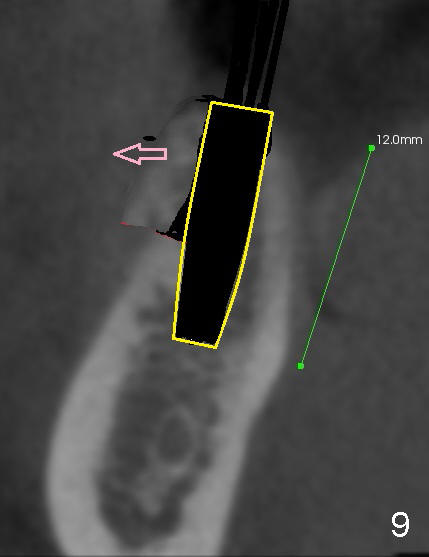

The patient is scheduled to return for implant placement 3 weeks later. The red lines in Fig.4 (CT coronal section) represent bony cuts in the ridge. A transverse incision is made over the top of the ridge with minimal exposure of the ridge. A curved osteotome is inserted into the upper bony cut (Fig.5). As the chisel is tapped in, the buccal segment moves buccally (Fig.6 pink arrow). When the chisel is withdrawn, a pilot drill is used to initiate osteotomy (Fig.7). As drills increase in diameter, the buccal segment continues moving buccally (Fig.8). Finally a bone-level implant (4.1 or 4.5x12 mm, Fig.9) or sub-crestal implant (4 or 4.5x8) is placed. Will the ridge split work?